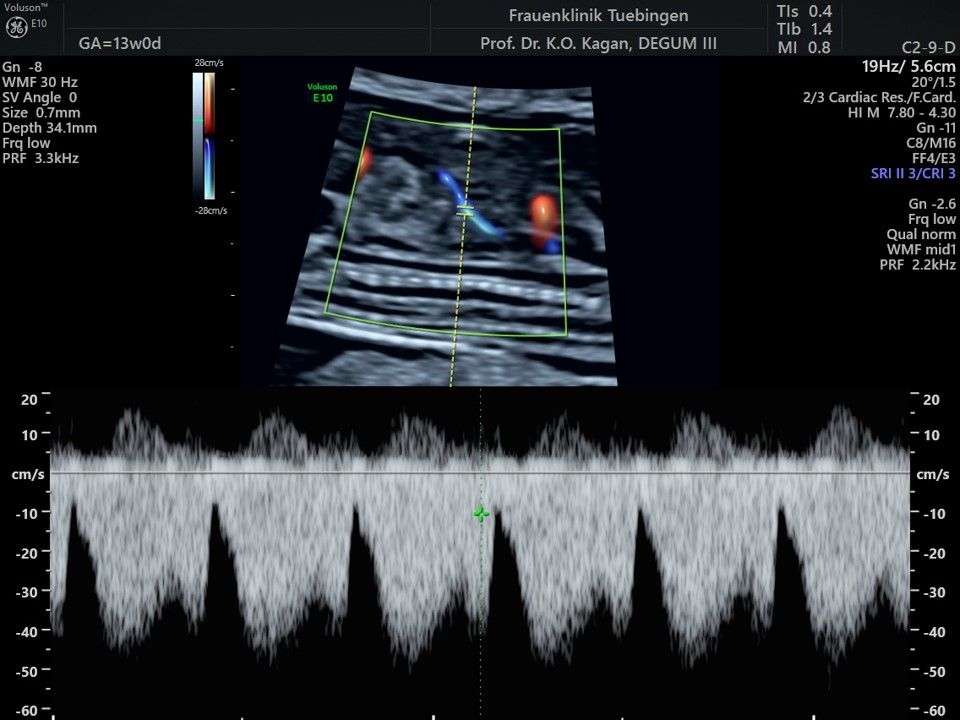

Mithilfe des Ersttrimester-Screenings kann das persönliche Risiko einer Präeklampsie bestimmt werden. Dazu wird die Vorgeschichte der Schwangeren, der aktuelle Blutdruck, das Ergebnis der Ultraschalluntersuchung (Widerstand in den Gebärmutter-nahen Gefäßen) und der Blutabnahme bei Ihnen (PAPP-A) kombiniert. Sollte das Risiko über 1:100 sein, empfehlen wir die tägliche Einnahme von Aspirin 150mg bis zu 35.SSW und eine gezielte Überwachung der weiteren Schwangerschaft.

Auch hier gilt wieder, dass der Untersuchung eine Aufklärung und Beratung vorausgeht und die Ergebnisse nach Abschluss der Untersuchung ausführlich besprochen werden.